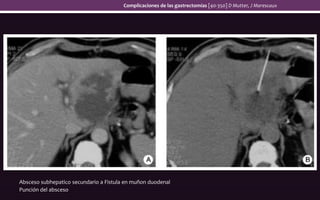

Absceso subhepatico secundario a Fistula en muñon duodenal

Punción del absceso